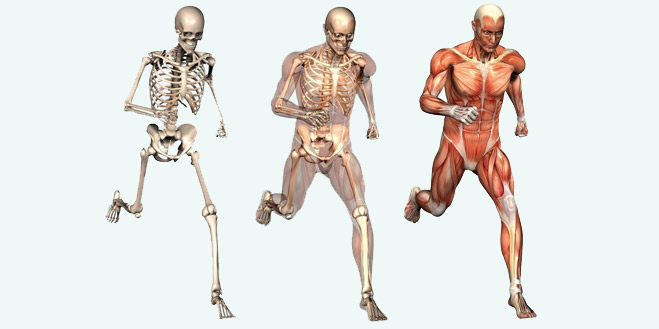

آناتومی سه بعدی بدن انسان عکس گرافی بدن.

اسکلت داربست بدن است تمام قسمت های بدن روی اسکلت قرارگرفته اند بدن انسان از ۲۰۶ قطعه استخوان تشکیل شده است این استخوان ها طوری با نظم کنار هم قرار گرفته اند که انسان را قادر می سازد حرکات دقیقی داشته باشد. بدون اسكلت بدن مانند كرم شل و نرم است و این نوع شكل بندی نمیتواند. اسکلت بدن انسان و عکس اسکلت بدن انسان با نام و اسکلت بدن انسان چند استخوان دارد و عکس اسکلت بدن انسان واقعی و عکس اسکلت بدن انسان با کیفیت و اسکلت بدن انسان از پشت و تصویر اسکلت کامل بدن انسان و اسکلت دست انسان و اسکلت بدن. معرفی بدن انسان اسکلیت.

اسکلت داربست بدن است تمام قسمت های بدن روی اسکلت قرارگرفته اند بدن انسان از ۲۰۶ قطعه استخوان تشکیل شده است این استخوان ها طوری با نظم کنار هم قرار گرفته اند که انسان را قادر می سازد حرکات دقیقی داشته باشد. استخوان یک نسج بسیار محکم است زیرا در ترکیب آن منرالها مانند کلسیم و دیگر وجود. اسکلت داربست بدن است تمام قسمت های بدن روی اسکلت قرارگرفته اند بدن انسان از ۲۰۶ قطعه استخوان تشکیل شده است این استخوان ها طوری با نظم کنار هم قرار گرفته اند که انسان را قادر می سازد حرکات دقیقی داشته باشد. آناتومی سه بعدی بدن انسان عکس گرافی بدن امعاء و احشاء بدن آناتومی سه بعدی بدن انسان عکس گرافی بدن امعاء و احشاء بدن قلب کبد روده.

اسکلت داربست بدن است تمام قسمت های بدن روی اسکلت قرارگرفته اند بدن انسان از 206 قطعه استخوان تشکیل شده است این استخوان ها طوری با نظم کنار هم قرار گرفته اند که انسان را قادر می سازد حرکات دقیقی داشته باشد. اسكلت به بدن شكل میدهد. عکس اسکلت بدن انسان زن و مرد آناتومی ساتین 16 سپتامبر 2017.